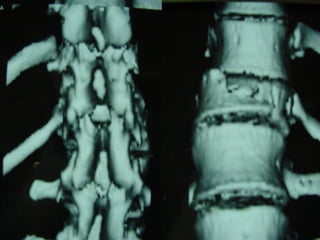

3D CT -SCAN

 AANN.. PPEERR..

 FF –– 2222 yyrrss

 FFaallll

 LLeevveell :: TT1122

 TTyyppee :: AA33..33

 AA..SS..II..AA.. :: EE